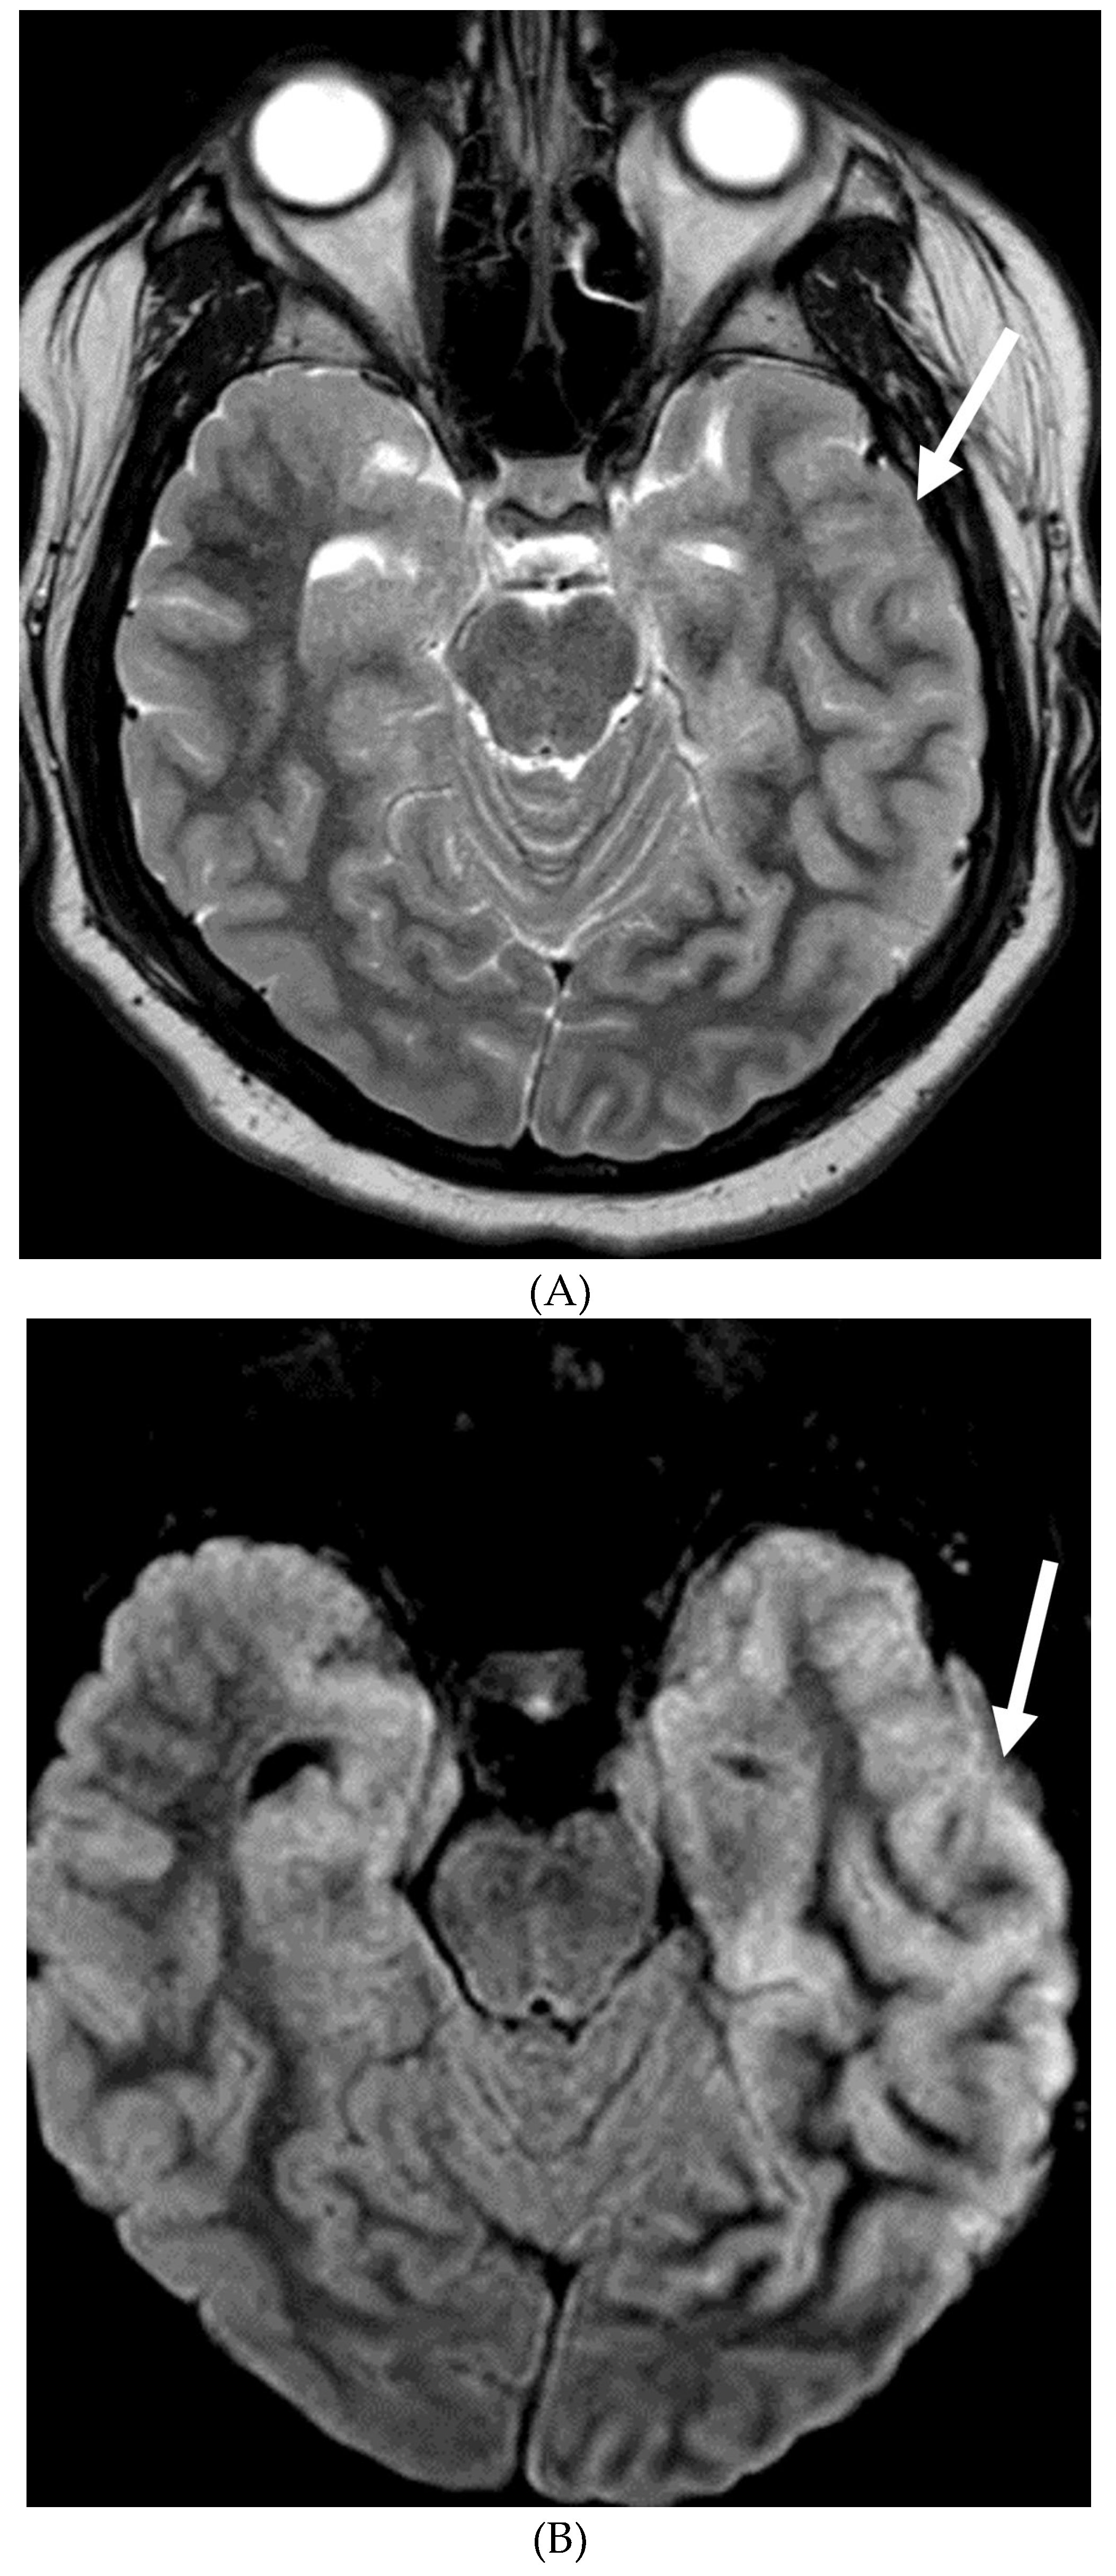

MOYA MOYA

- Horie N, Morikawa M, Nozaki A, Hayashi K, Suyama K, Nagata I. "Brush Sign" on susceptibility-weighted MR imaging indicates the severity of moyamoya disease. AJNR Am J Neuroradiol. 2011 Oct;32(9):1697-702. Epub 2011 Jul 28. PMID: 21799039; PMCID: PMC7965393. [CrossRef]

- Ohta T, Tanaka H, Kuroiwa T. Diffuse leptomeningeal enhancement, "ivy sign," in magnetic resonance images of moyamoya disease in childhood: case report. Neurosurgery. 1995 Nov;37(5):1009-12. PMID: 8559324. [CrossRef]

- Maeda M, Tsuchida C. "Ivy sign" on fluid-attenuated inversion-recovery images in childhood moyamoya disease. AJNR Am J Neuroradiol. 1999 Nov-Dec;20(10):1836-8. PMID: 10588105; PMCID: PMC7657767.

- Liu ZW, Han C, Wang H, Zhang Q, Li SJ, Bao XY, Zhang ZS, Duan L. Clinical characteristics and leptomeningeal collateral status in pediatric and adult patients with ischemic moyamoya disease. CNS Neurosci Ther. 2020 Jan;26(1):14-20. Epub 2019 Apr 13. PMID: 31875482; PMCID: PMC6930821. [CrossRef]

- Komiyama M, Nakajima H, Nishikawa M, Yasui T, Kitano S, Sakamoto H. Leptomeningeal contrast enhancement in moyamoya: its potential role in postoperative assessment of circulation through the bypass. Neuroradiology. 2001 Jan;43(1):17-23. PMID: 11214642. [CrossRef]